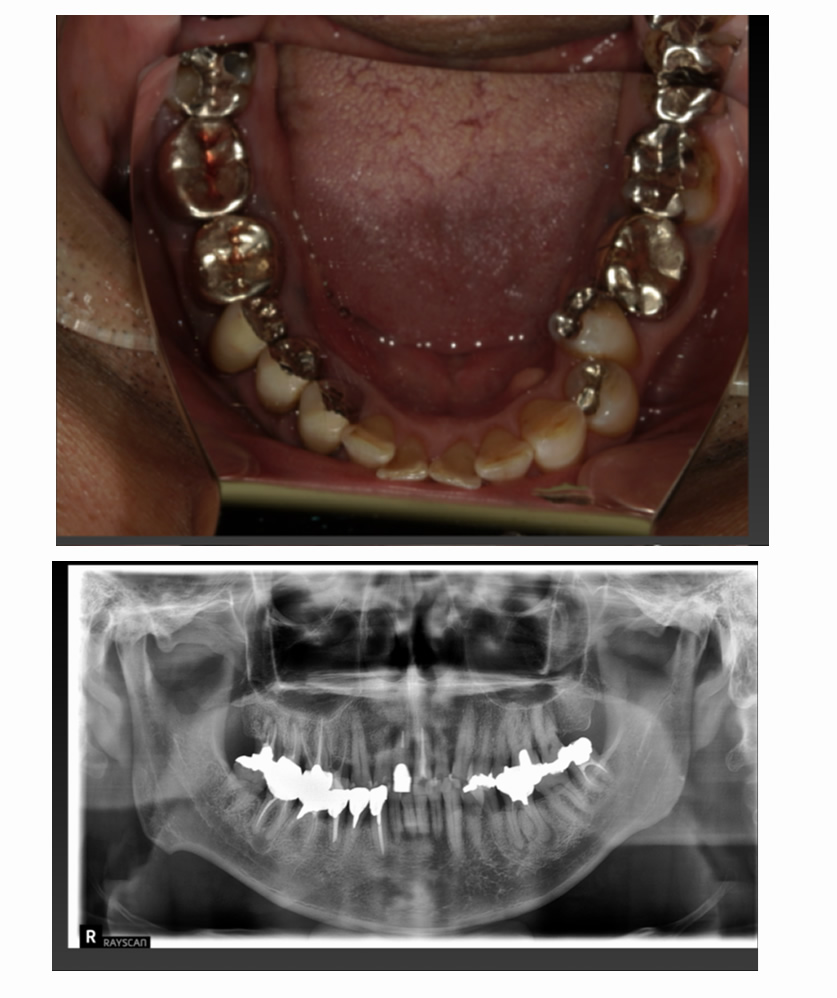

04 症例

04 右下の歯が割れ、左上が入れ歯なのでインプラント希望

Before

After

| 治療内容 | 右下の歯が割れている、左上が入れ歯なのでインプラント希望 |

| 患者さま | 50代男性 |

| 主訴 | 根が割れていて痛いのと、入れ歯の管理が大変なのでインプラントにしたい。 |

| 治療期間(目安) | 3ヶ月 |

| 治療費(税込:目安) | ¥984,500 |

| リスク | 術後に多少の痛みや腫れが出ることがある。歯肉退縮がおきると、歯と歯肉の間に隙間が生じることがあります。 |